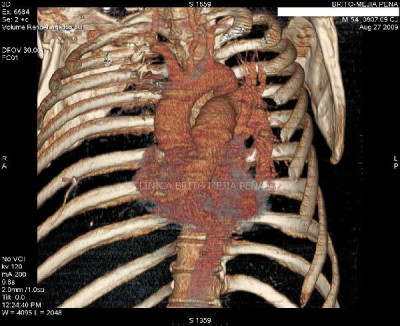

Trombosis arteria pulmonar 3D